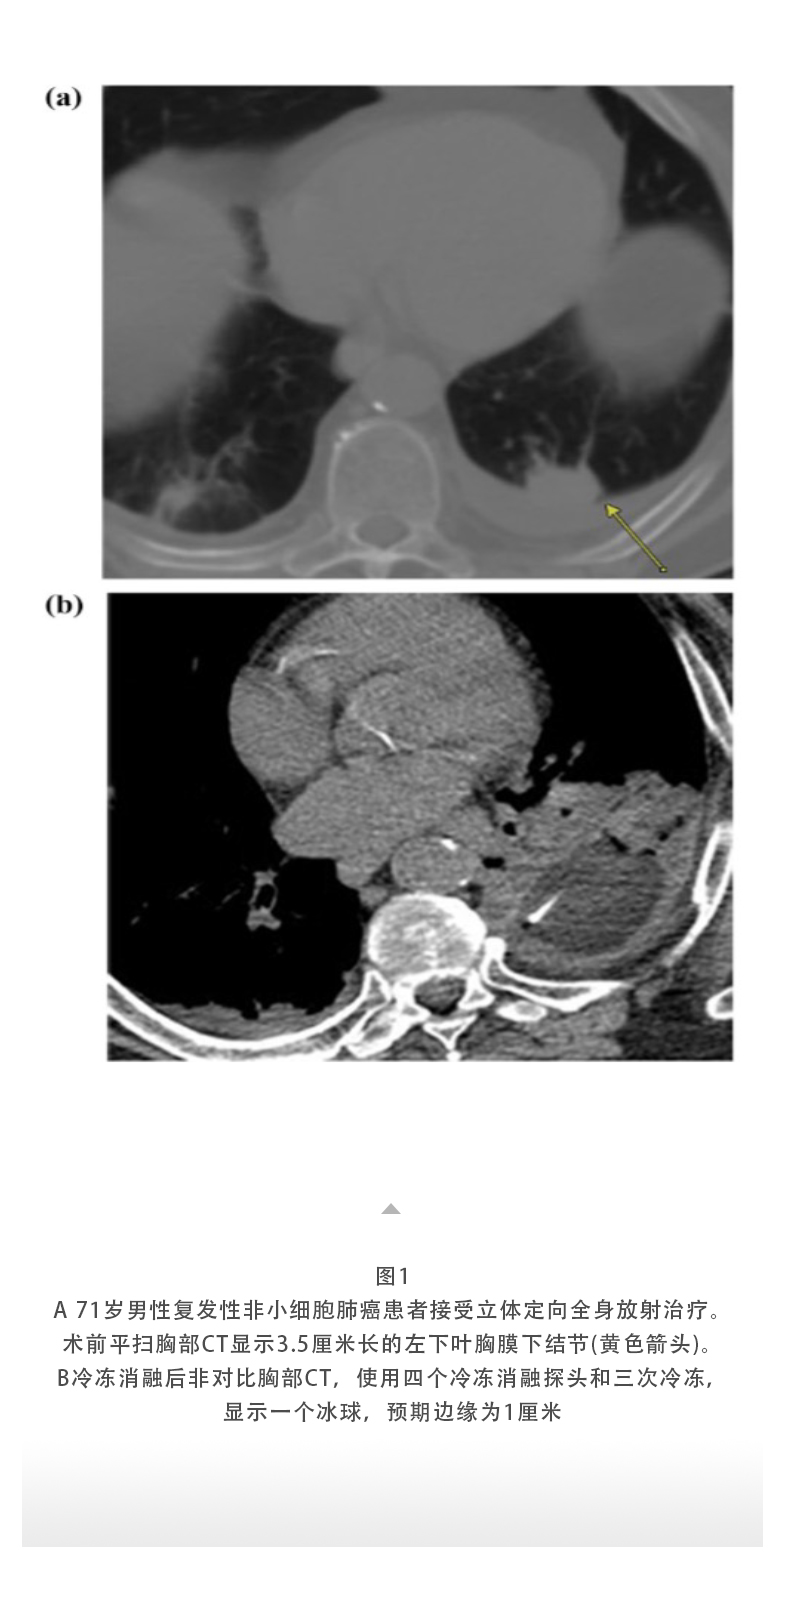

上一页:【HYGEA·科研资讯】冷冻消融治疗肺癌